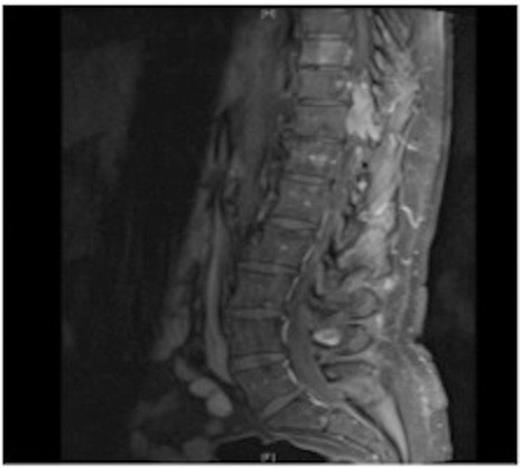

MRI showing the T10-11 extra-dural tumour with erosion of the T12 pedicle

Due to the low-grade nature of the tumour and the spinal cord compression the advantages and disadvantages of surgery versus radiotherapy were discussed with the patient who then agreed to have the tumour surgically removed.